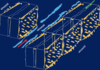

Explain the image

Liver, vessels injected with Prussian blue in gelatin. Green lines delineate the boundary of a liver lobule.

What are the 3 ways to describe liver lobules

§Classic liver lobule (blue)

§Liver acinus (red)

§Portal lobule (green)

8.6.1

Explain the image

Comparison of the classic liver lobule, portal lobule, and liver acinus. The area indicated in blue shows the territory of each of the three units relating to liver organization and function. The classic lobule has the terminal hepatic venule (central vein) at the center of the lobule and the portal canals containing portal triads at the peripheral angles of the lobule. The portal lobule has a portal canal at the center of the lobule and terminal hepatic venules (central veins) at the peripheral angles of the lobule. The liver acinus has distributing vessels at the equator and terminal hepatic venules (central veins) at each pole.